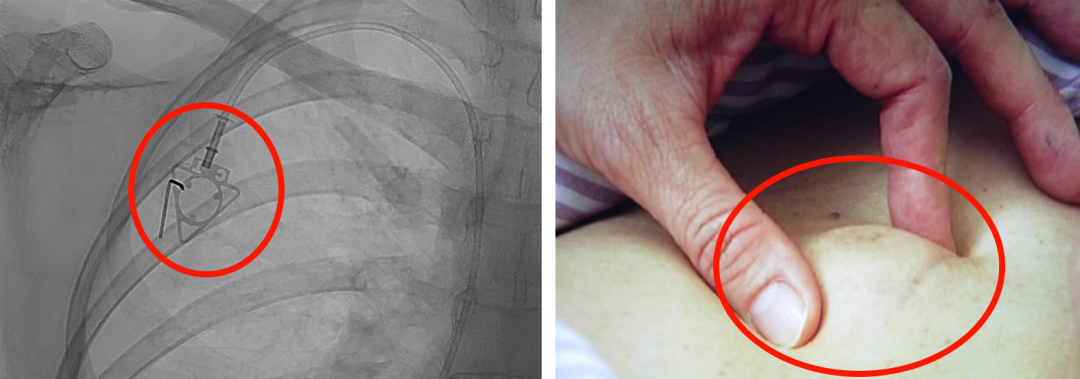

輸液港,臨床上也稱為PORT,是為了減輕藥物對(duì)患者血管刺激而置入體內(nèi)的專業(yè)輸液裝置。它分為三部分:無損傷針、置入靜脈的導(dǎo)管、埋藏在皮下與輸液針連接的注射座(港體)。注射座連接插入大靜脈的導(dǎo)管形成長期血管通路,發(fā)揮類似港口的作用,故稱作“輸液港”。

(1)輸液港輸注藥物直達(dá)大血管,手臂不會(huì)產(chǎn)生明顯的不適。由于每次穿刺的是皮下置入的港,可以減少針頭對(duì)血管的刺入次數(shù),操作簡單,對(duì)患者的血管起到保護(hù)作用;